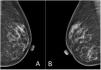

Imágenes radiológicas de las mamografías de mama izquierda (A) y de mama derecha (B). Se observa la simetría entre ambas mamas, con adecuada distribución del tejido glandular y sin presencia de distorsiones en la arquitectura ni calcificaciones sospechosas. Piel y complejo del pezón sin alteraciones.